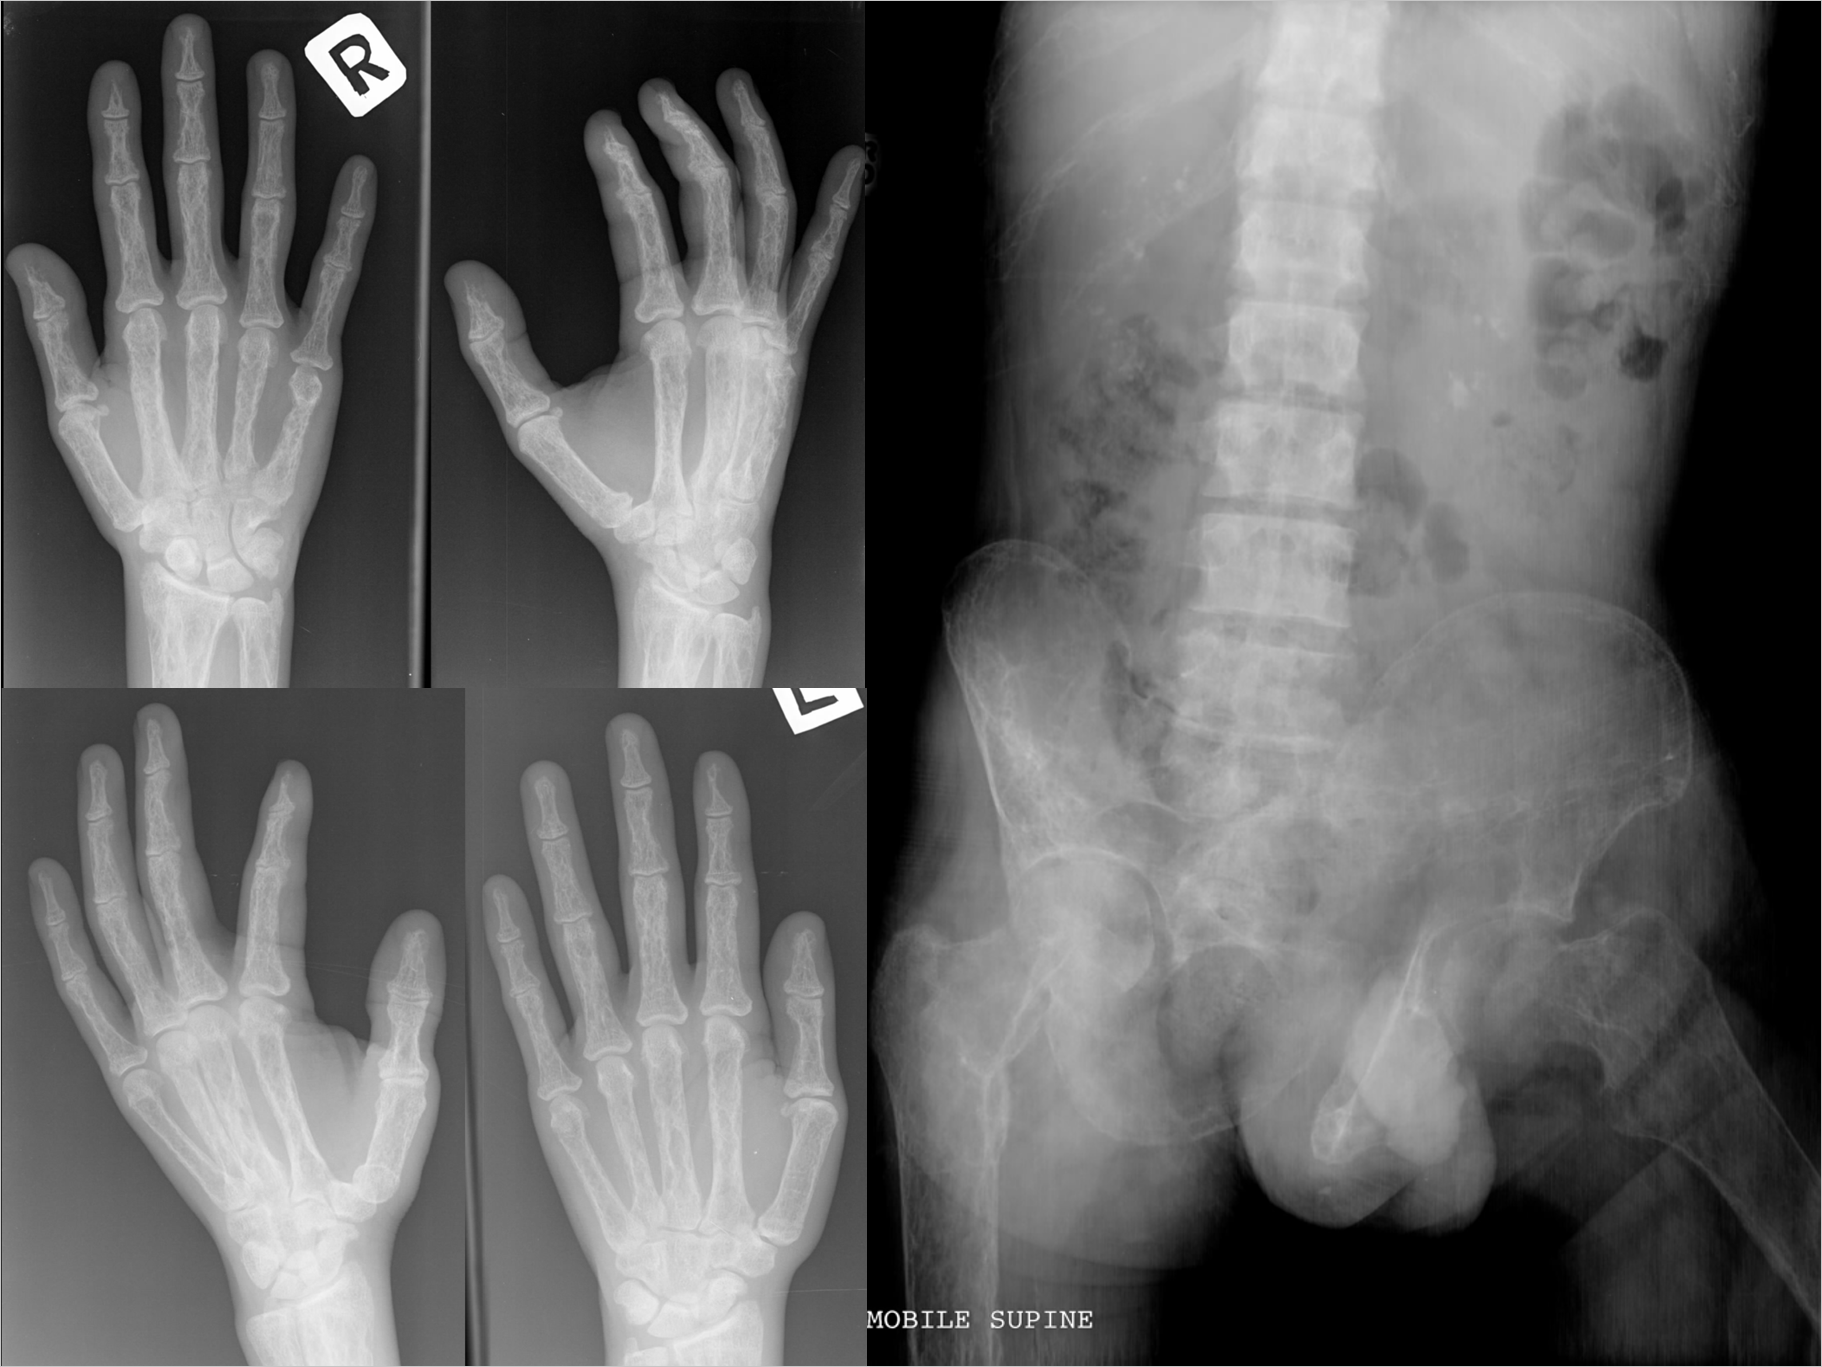

36yo male attended ED with left #femur (mid-shaft) incurred during soccer practice.

[View Skeletal XRays]